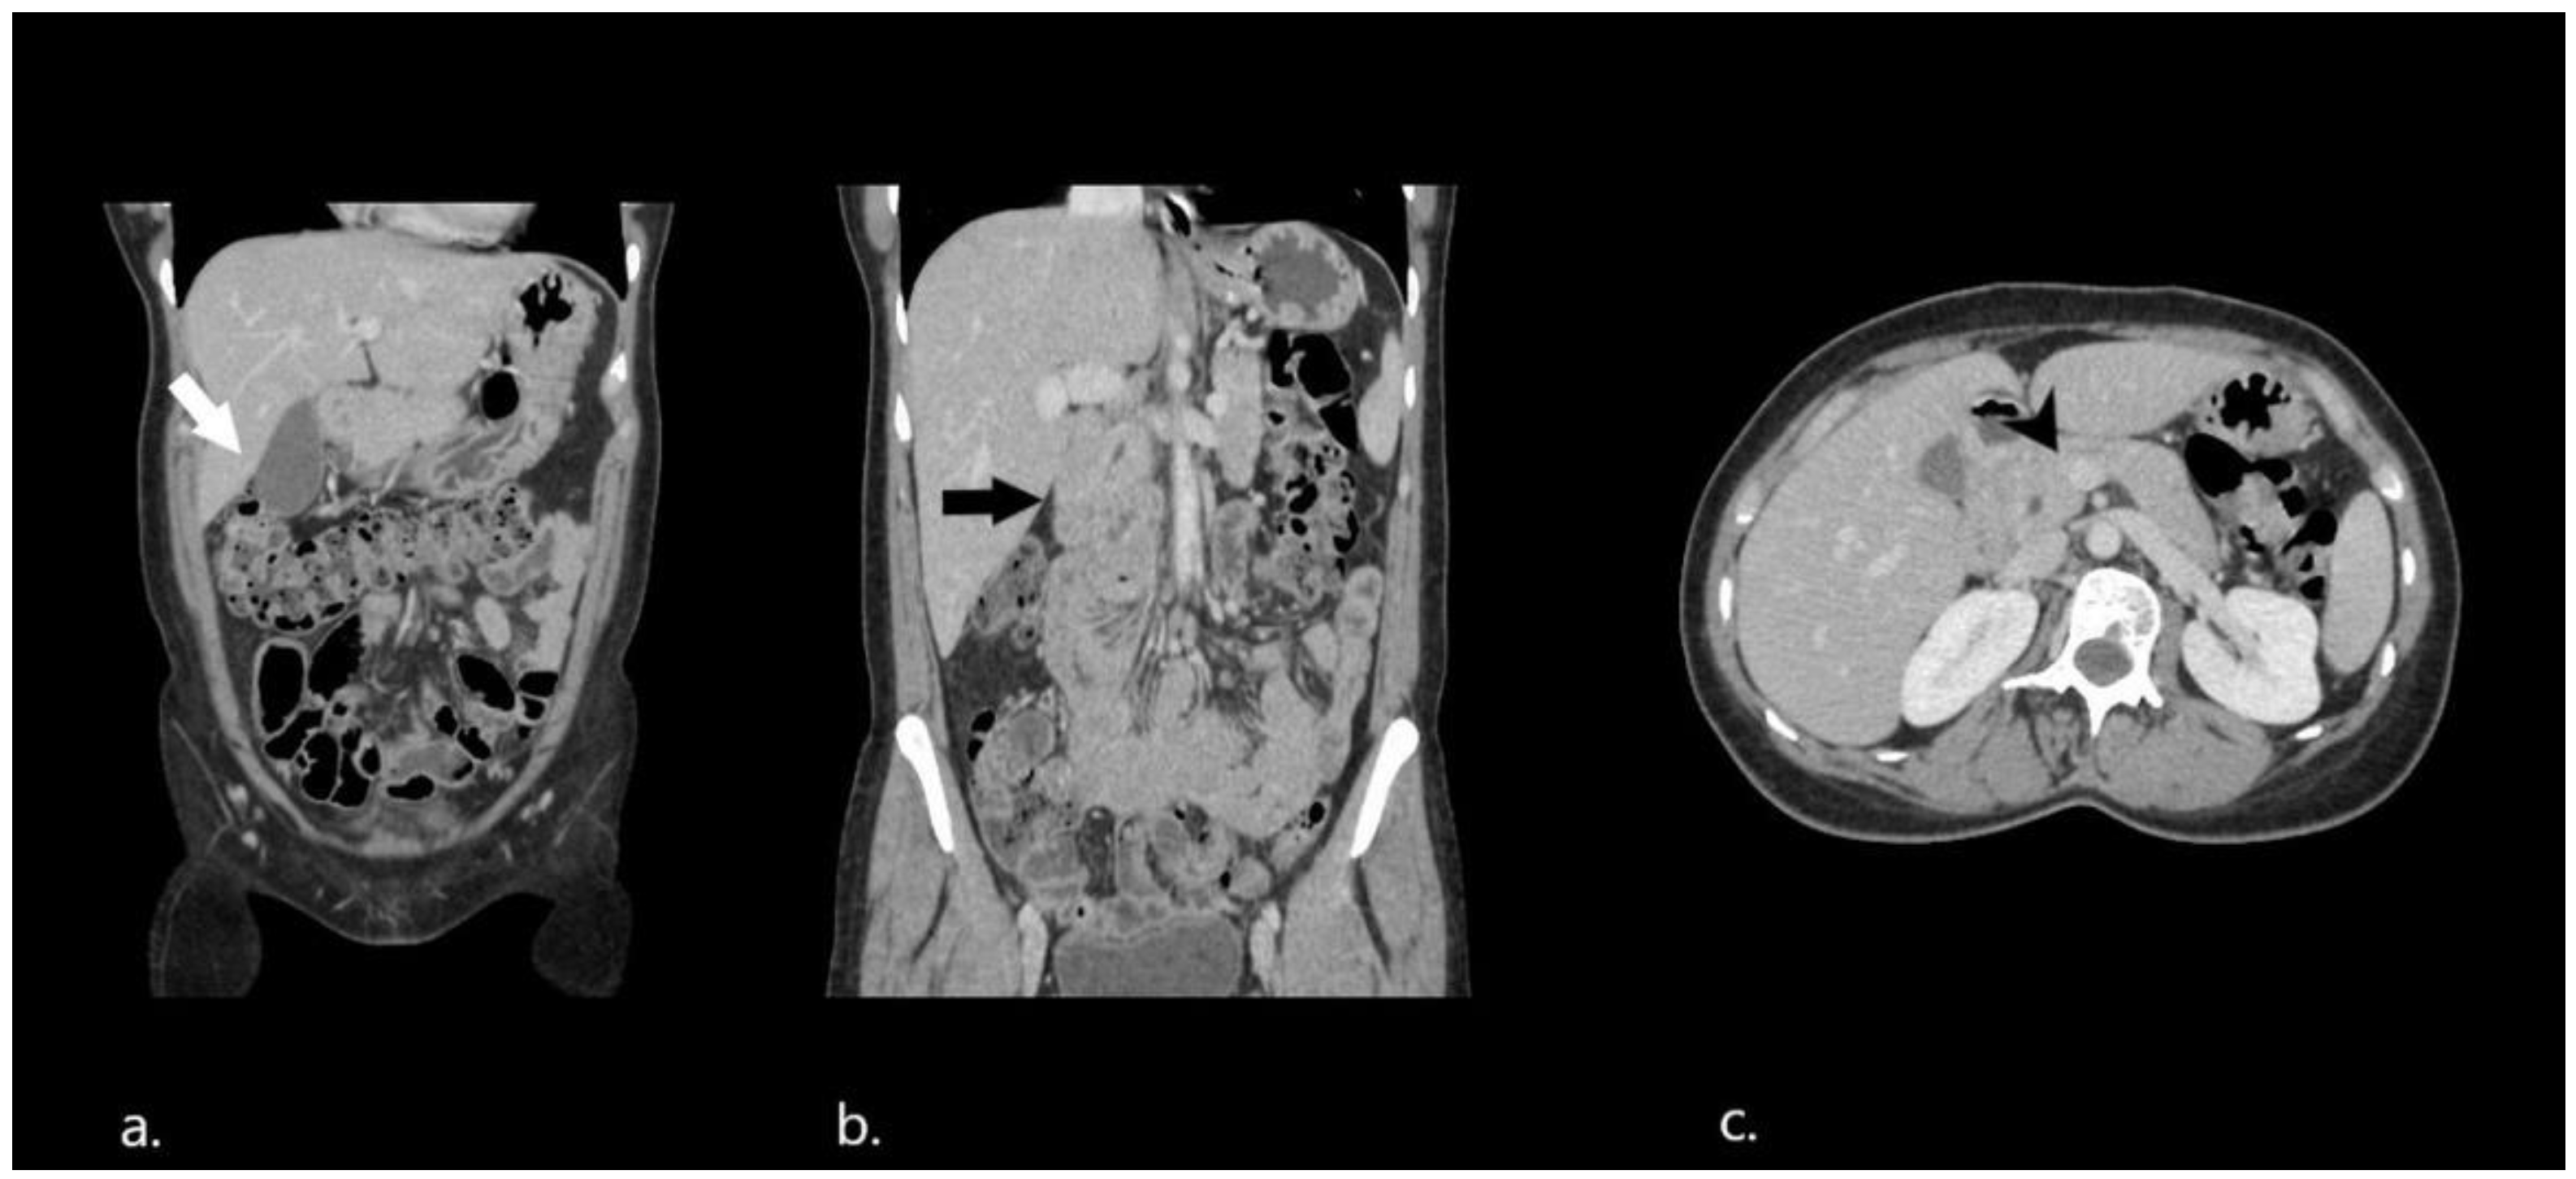

2. Case Presentation